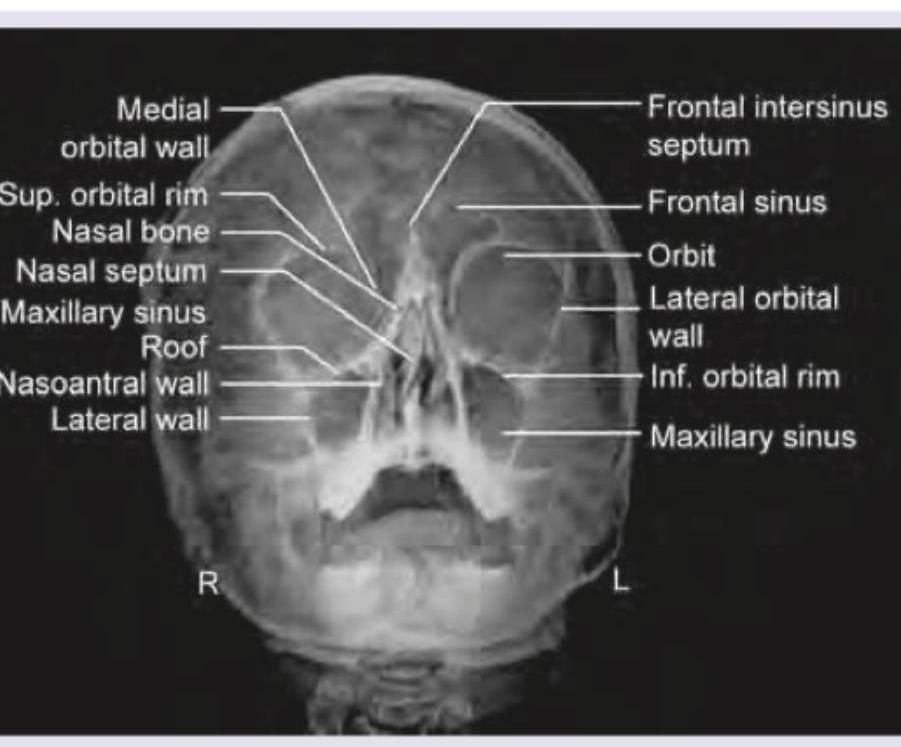

The given X-ray of paranasal sinuses shows which view?

Explanation: ***Waters' view*** - This view, also known as the **occipitomental view**, is primarily used to visualize the **maxillary sinuses**. - Key features include the **maxillary sinuses** being projected above the petrous ridges, allowing clear visualization of their floors and the inferolateral orbital walls. - The patient's mouth is open in this view, and the **petrous pyramids are projected below the maxillary sinuses**. *Caldwell view* - Also known as the **occipitofrontal view**, it primarily visualizes the **frontal sinuses** and anterior ethmoid air cells. - In a Caldwell view, the **petrous ridges** obscure the lower third of the orbits. *Orthopantomogram* - An **Orthopantomogram (OPG)** is a panoramic dental X-ray that shows all the teeth and surrounding bones in a single image. - It provides a broad view of the **mandible** and **maxilla**, which is not depicted in the image. *Luc's View* - Luc's view is an uncommon projection, sometimes referring to a **lateral view of the maxillary sinus** or a **basal/submentovertex view**. - It is used to visualize the **sphenoid sinus** and **posterior structures**, not the maxillary sinuses as prominently shown in this image.

Explanation: ***Maxillary*** - The image provided is a **Waters' view** (occipitomental view) X-ray of the paranasal sinuses, which is primarily used to visualize the **maxillary sinuses**. - In a Waters' view, the **petrous ridges** (dense bone at the base of the skull) are projected below the maxillary sinuses, allowing for a clear view of these sinuses. *Frontal* - While the **frontal sinuses** are visible in a Waters' view, they are generally better visualized in a **Caldwell view** (occipitofrontal view) or lateral view. - In this projection, their visualization can be obscured by other bony structures, and they are not the primary focus. *Ethmoidal* - The **ethmoidal sinuses** are typically comprised of multiple small air cells located between the orbits and are best seen on a **Caldwell view** or specialized oblique views. - In a Waters' view, their evaluation is limited due to superimposition of other facial bones. *Sphenoidal* - The **sphenoidal sinuses** are located deep within the skull, inferior to the sella turcica, and are quite difficult to visualize on standard plain radiographs like the Waters' view. - They are best assessed using a **lateral view of the skull** or advanced imaging like **CT scans**.